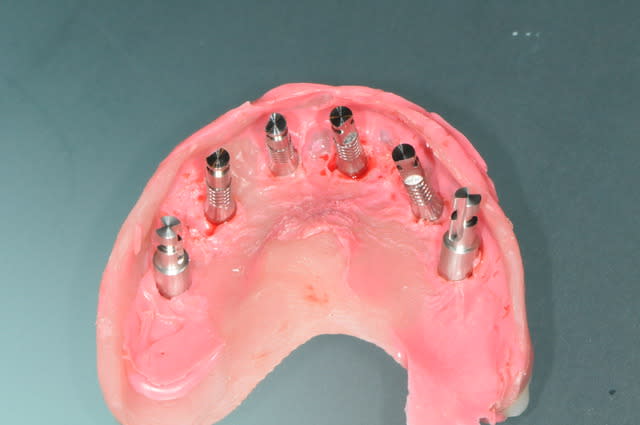

depuis que je me suis acheté une imprimante 3D, je fais moi même mes guides chirurgicaux.

j'ai trouvé ça il y a quelques mois avec l'intention de réaliser des petits objets pour les gamins et des guides pour mes chirurgies.

voici un cas en images, j'espère que ça plaira, ça fait un moment que je n'ai rien posté sur nonol et suis en manques de critiques et de compliments.

la patiente a été opérée hier et j'ai mis ses prothèses aujourd'hui.

la veille de l'intervention j'ai imprimé le model 3 D.